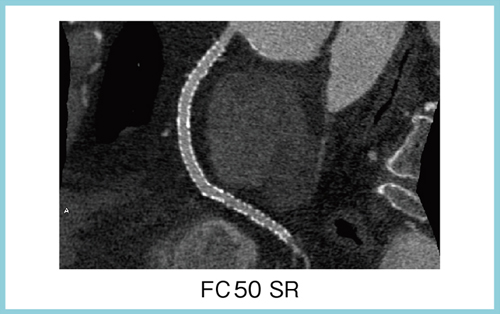

Aquilion ONEのアキシャルスキャンでは,1回のスキャンで心臓全体をカバーし,ブレのない高画質のデータが得られる。1心拍で撮影されたボリュームデータから再構成を行うため,従来のような心位相の相違や位置の違いによるズレがない画像が得られる。また,不整脈に対しても,システム側で自動的に対応する機能を搭載し,全体として心臓検査のワークフローが改善する。さらに,1回転1心拍の撮影によって,被ばく線量も従来の1/3〜1/4に低減されている。図1はステント留置後のRCAの画像だが,ステント内腔がきれいに描出されている。ステント留置症例では,高分解能の画像再構成によって,さらにステントのアーチファクトを減らし,ズームによって内腔の評価が可能になる。

図1 1心拍のアキシャルスキャンによる冠動脈CTA